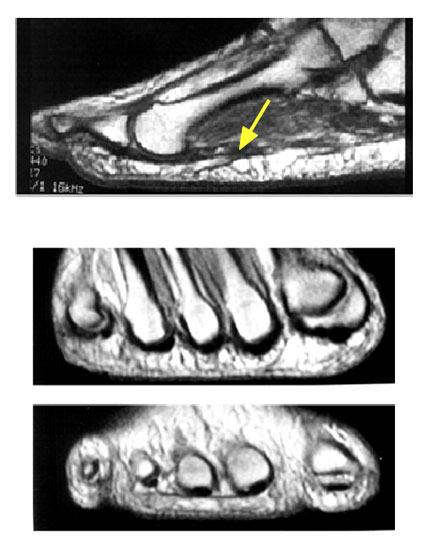

MRT Aufnahmen zeigen das plantare Fettpolster zwischen den beiden Schichten der Plantaraponeurose.

<div style="text-align:left">(a) In der sagitalen Schnittführung des MRTs ist erkennbar, wie die oberflächliche und die tiefe Schicht der Plantaraponeurose

Abbildung 5